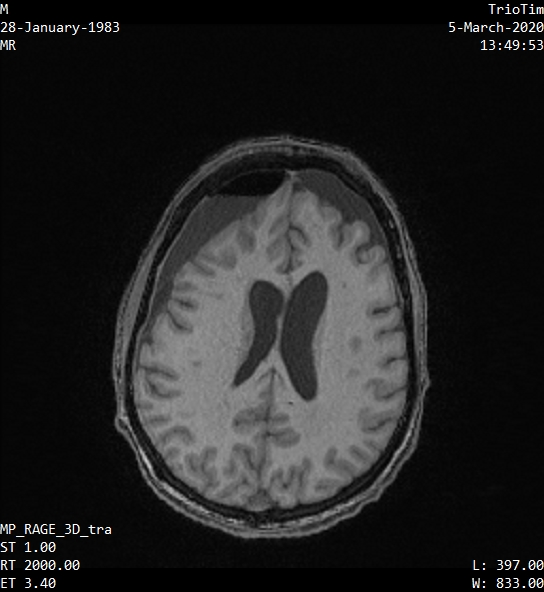

A 37-year-old male K. presented in the Clinical Insitute of the Brain (CIB) in the beginning of March 2020 with chronic disorder of consciousness after severe traumatic brain injury acquires in road accident, complicated with hypoxia – patient was stuck in the car for 40 minutes. That collision took place in the end of December 2019, immediately after the ambulance arrived patient was transported to the neurosurgery clinic. CT scan showed an acute subdural hematoma, diffuse axonal injury, massive subarachnoid hemorrhage, cerebral oedema, pneumocephalus and multiple facial skull fractures. 2 months later MRI showed massive gliotic changes and cerebral atrophy (Figure 2).

Figure 2 Patient’s K. MRI scan.